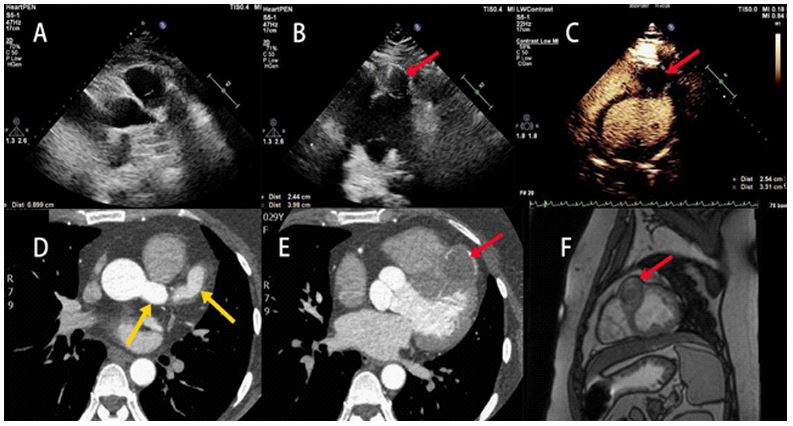

A 29-year-old woman presented with persistent chest pain for 2 days. Echocardiography revealed a dilated vessel on the left side of the aortic root (9 mm diameter; Figure 1A), and a localized hypoechoic bulge in the mid-anterior interventricular septum (24 mm × 40 mm; Figure 1B, red arrow). Myocardial Contrast Echocardiography (MCE) was performed using sulphur hexafluoride microbubbles. A well-defined hypoechoic area was observed anterior to the interventricular groove with the size of 25 mm × 33 mm. After high-energy microbubble destruction (flash imaging), the region showed no contrast enhancement (Figure 1C, red arrow). To further clarify the coronary artery condition, coronary CTA was performed. Coronary CTA demonstrated dilation of the left main coronary artery (15.6 mm) and proximal left anterior descending artery (14.5 mm) (Figure 1D, yellow arrows). The mid-segment formed a 32 × 31 mm aneurysm containing an intraluminal thrombus (Figure 1E, red arrow). To confirm the nature of the mass, a Cardiac Magnetic Resonance Imaging (CMR) examination was performed. CMR revealed an irregular tubular structure in the anterior interventricular sulcus with heterogeneous T2 signal intensity. Delayed enhancement sequences showed no significant enhancement, consistent with chronic thrombosis. The maximum cross-sectional area was about 3.6 cm × 2.8 cm (Figure 1F, red arrow). Multimodal imaging confirmed a left coronary artery aneurysm with thrombosis. Although childhood Kawasaki disease is the most common etiology of coronary artery aneurysms, the patient showed clinical improvement with anticoagulation and was discharged on rivaroxaban therapy.

Figure 1: (A) Echocardiography revealed a dilated blood vessel on the left side of the aortic root; (B) A localized low-echo bulge was observed in the front of middle segment of the anterior interventricular septum; (C) MCE A well-defined low-echo area was detected in front of the interventricular groove; (D) Coronary CTA showed the left main coronary artery and the proximal left anterior descending artery were dilated; (E) A middle segment was dilated to aneurysm with the widest diameter about 32 mm × 31 mm; (F) CMR The proximal luminal signal was similar to that of the blood pool, and there is a mixture of high and low T2 signals in the distal cavity.